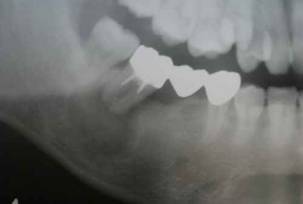

術前。下顎第一大臼歯 3根管 (抜髄)インレーの下の虫歯が歯髄(神経)にまで及んでいました。